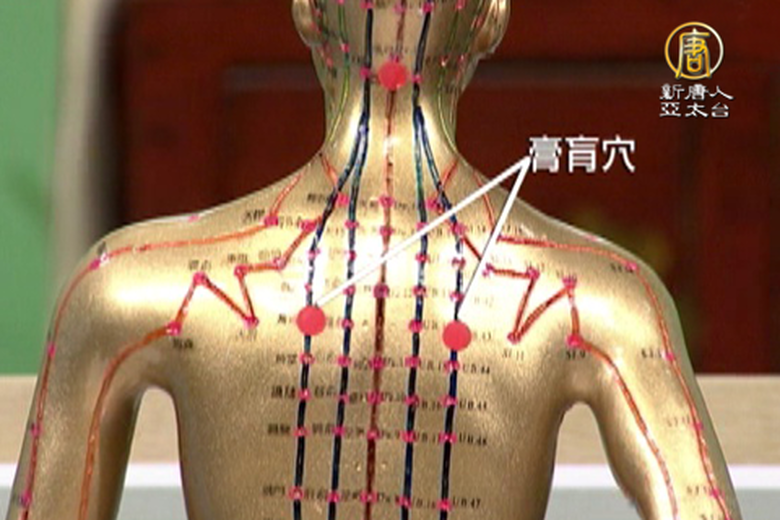

什麼是「病入膏肓」?膏肓痛要怎麼辦? |談古論今話中醫(265)

2015-12-11 14:42:18古人稱膏肓是在我們現在的心臟部位。病入膏肓通常是指事情已經到了難已挽回的地步。 我們人身上真的是有膏肓穴。病入膏肓是怎麼個由來,以及它會有哪些痛的症狀。